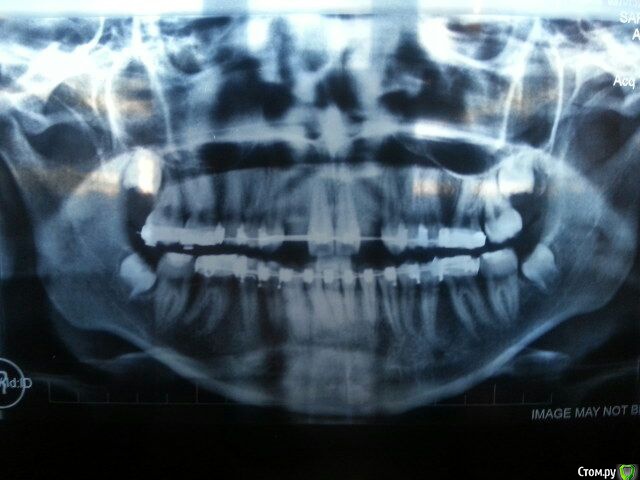

Амина Опубликовано 4 июня, 2016 Автор Поделиться Опубликовано 4 июня, 2016 (изменено) Здравствуйте. Мне очень нужен совет. Дочке 12 лет. Повели к стоматологу потому что зубки местами несколько неровные. Не критично, но всё же девочка же. В процессе выяснилось, что:1) у ребенка неправильный прикус. Норма - нижние зубы за верхними. Бывает, что нижние перед верхними. А у неё нижний и верхний ряд зубов ровненько на одной линии. В общем сказали, что надо ставить брекеты обязательно - исправлять кривизну зубов и неправильный прикус.2) у дочки нет двух верхних передних резцов. То есть у всех впереди вверху посерединке четыре резца и затем по бокам идут клыки. А у неё два резца и следом клыки по бокам. На снимке (панорамная съемка) видно, что нет даже зачатков вторых резцов. Врач говорит, что выхода два1) раздвинуть с помощью брекетов зубы увеличив расстояние между резцами и клыками. Затем ребенок лет до 18-ти должен ходить с какой-то чуть ли не вставной челюстью. После чего ей поставят имплантанты2) сдвинуть зубы чтобы между ними не было большого расстояния и затем (попозже) подпилить клыки.Нужно это для того, чтобы в зрелом возрасте из-за отсутствия двух резцов у дочери не было больших зазоров между зубами.Мне первый вариант не нравится категорически (вставные челюсти, имплантанты - зачем так ребенка мучить). Насчет второго - не слишком устраивает подпиливание. Врач также говорит, что отсутствие этих зубов не аномалия какая-то, сейчас многие дети такие. Посоветуйте, что нам делать. Заранее спасибо! Прошу прощения за корявое изложение - не владею специальными терминами. в 2009 году была такая история. но в итоге мы пошли по первому варианту снимок 2015 года Изменено 4 июня, 2016 пользователем Амина Ссылка на комментарий

Амина Опубликовано 4 июня, 2016 Автор Поделиться Опубликовано 4 июня, 2016 ну и вот то, что было изначально старое 2009 год.pdf Ссылка на комментарий